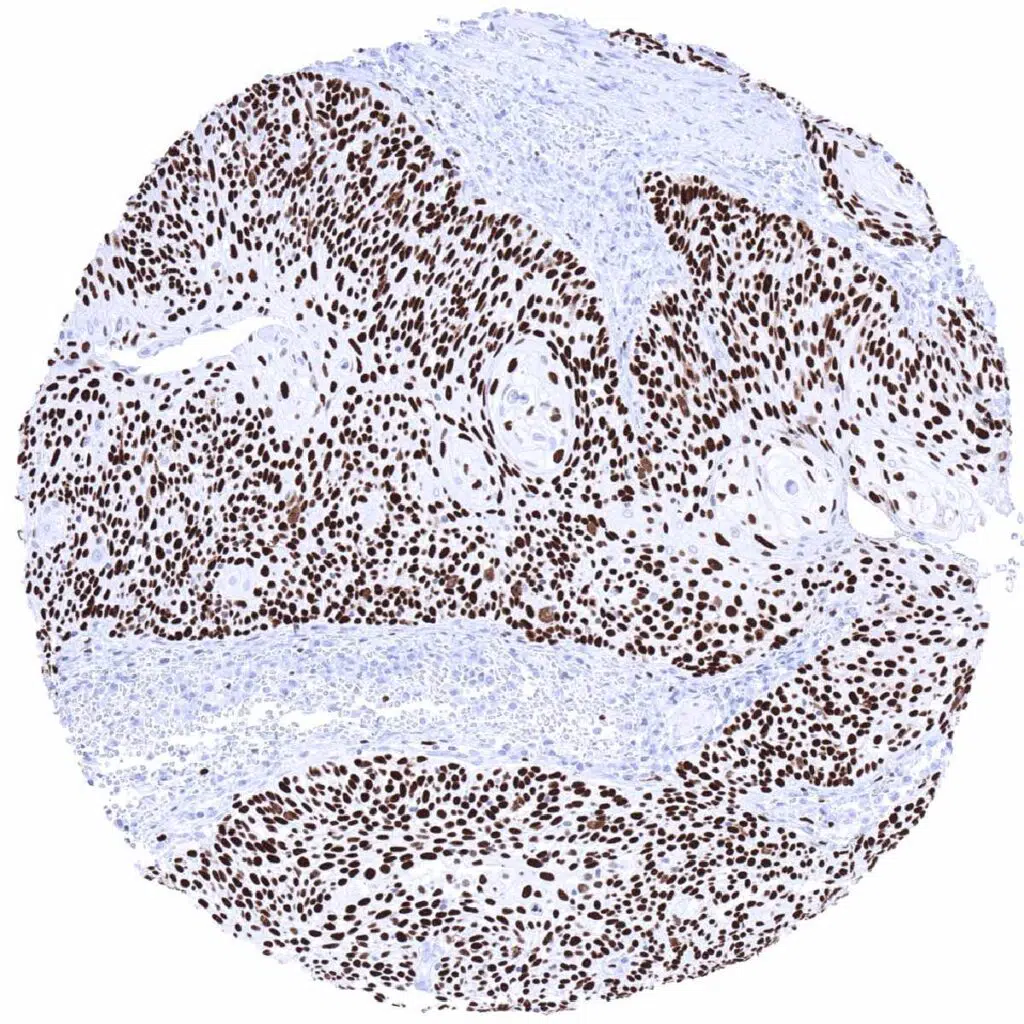

Urinary bladder- Muscle-invasive urothelial carcinoma depicting strong MCM7 positivity in all tumor cells